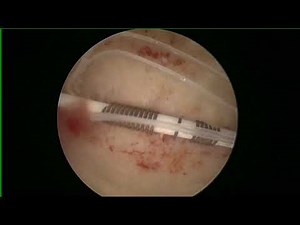

HYSTERSCOPIC Copper T removal

281K amharc

4 Noll 2019

YouTube

Dr. Yashodhan Deka